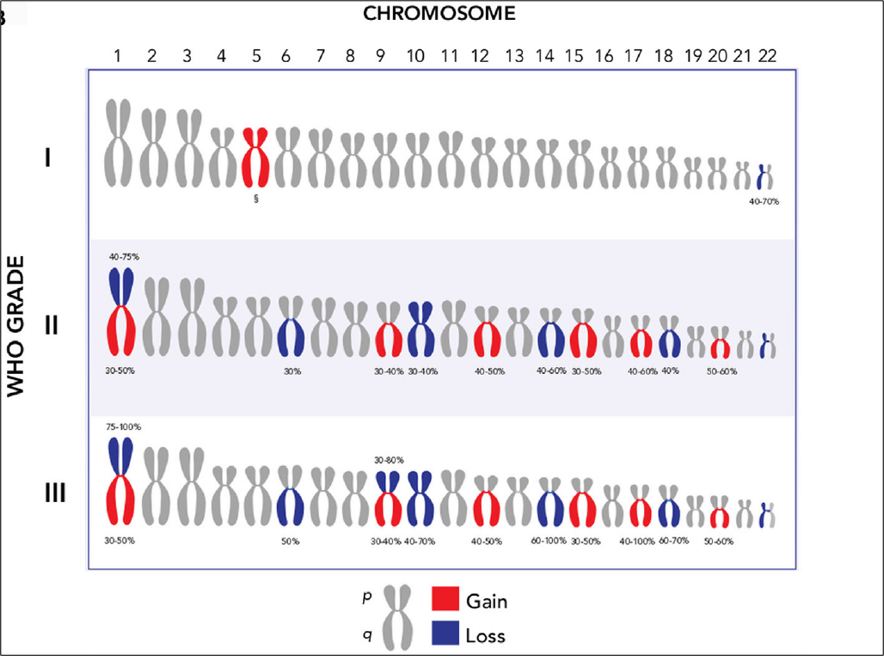

世界卫生组织(WHO)分类方案根据显微镜下的细胞类型将脑膜瘤分成15种组织亚型。这些组织学亚型分为三个等级(WHO I-III级),组织分型通常根据细胞学特征反映肿瘤生长速率和复发的可能性。非典型脑膜瘤(WHO II级,占脑膜瘤病例的18%)表现出组织和细胞异常增加。这些肿瘤的生长速度快于良性脑膜瘤,通常以脑部侵袭为特征。非典型脑膜瘤比良性脑膜瘤(WHO I级)复发的可能性更高。恶性脑膜瘤(WHO III级)显示细胞异常增加,并且比良性和非典型脑膜瘤的生长速度更快。恶性脑膜瘤比其他两种亚型更容易侵袭大脑并且复发频率更高。

脑膜瘤分子分型:脑膜瘤是常见的颅内原发性脑肿瘤,当前脑肿瘤的诊断模式是组织型和基因型的整合诊断。虽然目前脑膜瘤的诊断仍然引用传统的组织分型,但是分子检测在脑膜瘤瘤诊断和预后评估中的作用越来越大,尤其是检测复发相关的分子标志物。关于脑膜瘤分子分型的研究越来越趋于成熟,近期在柳叶刀肿瘤学期刊中发表了脑膜瘤6亚型的分子分型研究,其中恶性脑膜瘤通常携带有NF2,TERT基因启动子激活突变,CDKN2A基因缺失,1p和10号染色体缺失等分子特征。

阔然精准诊疗脑肿瘤产品CaptioX-M是一款以NGS技术为基础的检测产品。CaptioX-M用于脑膜瘤的分子诊断,涵盖了脑膜瘤复发相关的67个基因(NF2、TERTp、CDKN2A/B、ARID1A和BIP1等)、预后相关的染色体(22q、1p、5、10等)拷贝数变异和潜在靶向治疗相关基因的信息,脑膜瘤CaptioX-M可用于脑膜瘤患者分子分型、预后评估和辅助医生制定治疗策略。